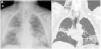

Varón de 82 años remitido al servicio de neumología por cuadro de disnea de 2 meses de evolución y desaturación, sin mejoría a pesar del tratamiento broncodilatador. Se le realizó radiografía de tórax (Rx) visualizándose condensaciones pulmonares bilaterales, y una tomografía computarizada (TC) de tórax objetivándose áreas de consolidación en lóbulo superior derecho (LSD) y lóbulo inferior izquierdo (LII) con reticulación asociada. Ante dichos hallazgos se decidió realizar una fibrobroncoscopia (FBC) que mostró inflamación difusa endobronquial. Durante el procedimiento se realizó aspirado bronquial no selectivo (BAS) y lavado broncoalveolar (LBA), sin complicaciones. Horas después, el paciente refirió aumento del perímetro cervical. La Rx de tórax mostró enfisema subcutáneo (fig. 1A) y la TC urgente neumomediastino (fig. 1B). El paciente fue tratado de forma conservadora con analgesia y oxigenoterapia obteniéndose mejoría de los síntomas, por lo que se recomendó seguimiento ambulatorio.

A) Radiografía de tórax posteroanterior que mostró enfisema subcutáneo y la persistencia de consolidaciones pulmonares a nivel de LSD y LII. B) Corte de reconstrucción coronal de la tomografía computarizada que evidenció neumomediastino y enfisema subcutáneo a nivel cervical de predominio derecho.